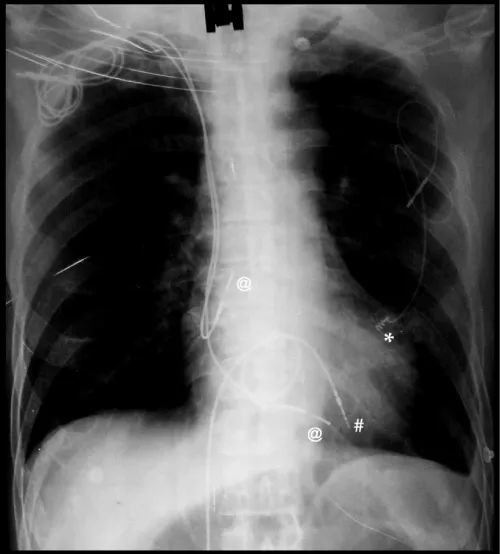

Figure 3: (Final position of pacemaker, new transiliac ventricular lead (#), old subclavian atrial (@) & ventricular leads (@), and epicardial lead (*) on thoracic-abdominal radiograph.

Figure 4: Abdomino-thoracic radiograph showing final position of old leads and new implant.